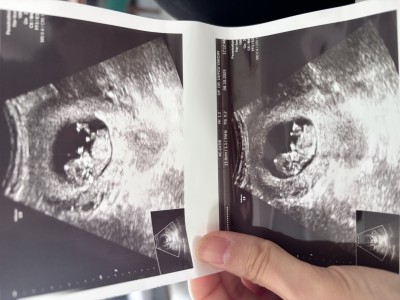

Kızlar 12haftada da cinsiyeti öğrenebilir miyim acaba birde siz bi yorumlar mısınız

Özel hastaneye gidiyorsan öğrenme şansın yüksek bu arada benim bebeğimin ultrason kağıdına çok benziyor erkek bence öğrenirsen mutlaka haber et merak ettim valla 😀

Valla gülüm benim de kesem böyle yuvarlak yani bence bu arkadaşımızın da erkek :)

Canım haber ver demişsin cinsiyeti öğrendim erkekmiş ☺️

Nub cikintisina bakarsak ben erkek gibi anladım ama bilemedim